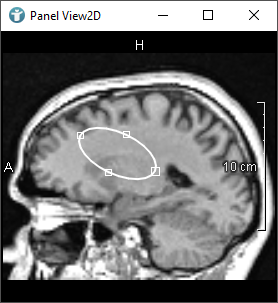

As mentioned, when creating CSOs, you can do this interactively by using an editor.

The following images show editors available in MeVisLab for drawing CSOs:

CSOs can also be grouped together. The following image shows two different CSOGroups. Groups can be used to organize CSOs, in this case to distinguish the CSOs of the right and the left lung. Here you can find more information about CSOGroups.